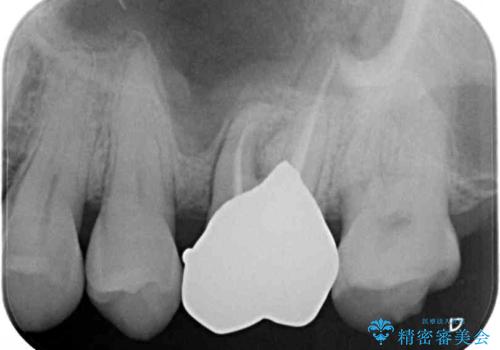

根管治療後に、歯根にまで及んでしまった破折部分を適切な位置に変更するため、歯槽骨の削除を伴う外科処置を行い、その後補綴治療を行うこととしました。

強い咬合力により歯が破折したため、補綴物は歯へのダメージの最も少ないゴールドクラウンを選択しました。